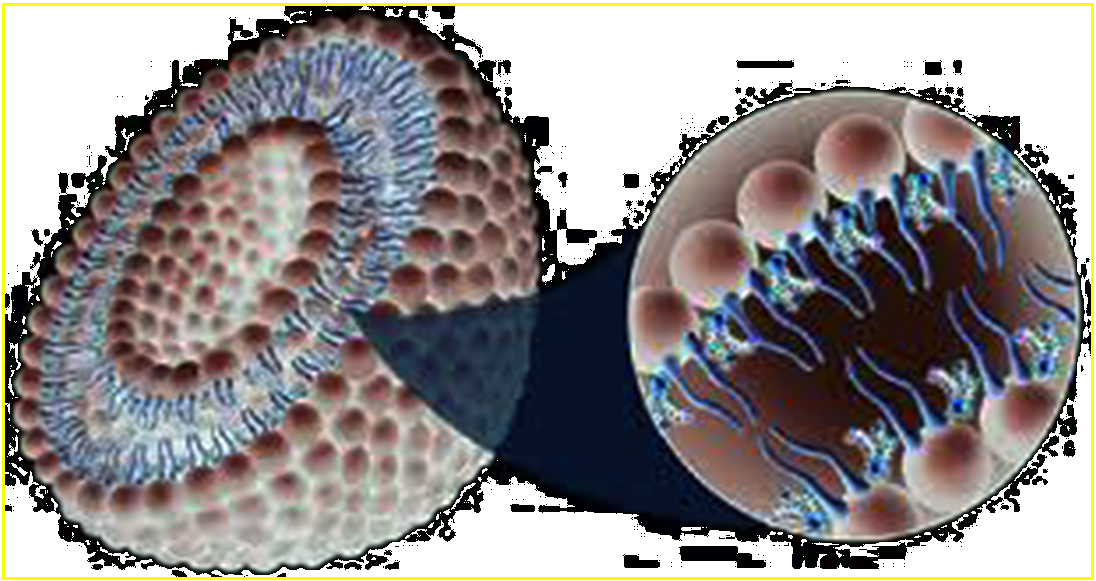

ARIKACE is a form of the antibiotic amikacin, which is enclosed in nanocapsules of lipids called liposomes. The study evaluated the ability of the ARIKACE liposomes to pass through patient mucus (sputum) ex vivo and to penetrate the bacteria's biofilm barrier in an established flow-cell in vitro model. The biofilm is a gel-like matrix in the lungs formed by colonies of Pseudomonas that create a protective barrier for bacteria. This prevents patients with cystic fibrosis (CF) from clearing infections even under aggressive antibiotic treatment. It is not practical to observe biofilm interactions in humans; therefore, the Center for Biofilm Engineering at Montana State University has developed a model to microscopically visualize the penetration of liposomes into Pseudomonas biofilms.

Separate studies showed that the small, neutrally charged ARIKACE liposomes facilitated antibiotic passage through the patient mucus layer and penetration into the Pseudomonas biofilm. Prior studies have shown that free aminoglycosides bind to patient mucus and thus have reduced bioactivity in killing Pseudomonas. Using microscopic techniques, the investigators were able to see that Arikace liposomes effectively penetrated and lodged into the spaces within biofilms, where the antibiotic can be released very close to the bacteria.

Another important study enabled investigators to identify bacterial virulence factors secreted by Pseudomonas in the biofilm that trigger release of amikacin from the liposomes. These factors are expected to be concentrated in and near the colonies of Pseudomonas growing in the biofilm within the static mucus of CF lungs. This area is an ideal target for antibiotics and the triggered release of amikacin resulted in what was essentially Pseudomonas suicide.

"We know for sure that the liposomes were interacting with, and accumulating in, the biofilm," said Dr. Garth James, Ph.D., director of medical projects at the Center for Biofilm Engineering at Montana State University and a co-author of the study. Montana State University's Center for Biofilm Engineering is the world's largest and oldest biofilm research center.

"You need a drug that can penetrate biofilm in order to kill the infection. This unique drug delivery mechanism may allow that to happen," Dr. James said. "By using an advanced delivery mechanism, you can keep the drug where it needs to be for a longer period of time. A "free" drug inhaled into the lungs would likely be cleared more rapidly."